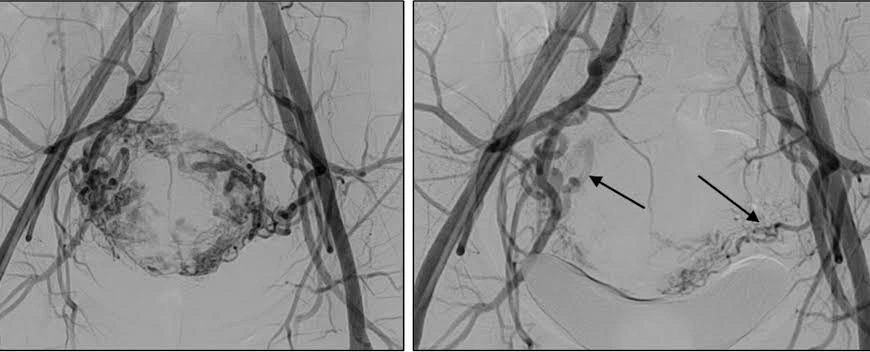

A small puncture is made to gain access to the artery, and a thin catheter is passed into the uterus to reach the uterine arteries under real-time imaging. Finally, small particles, which are aptly compared to sand grains in size, are infused to occlude smaller arteries supplying the fibroids. The particles will be lodged in these arteries and cause a reduction in blood flow to the fibroids, causing them to shrink.

Both uterine arteries are usually handled through the same access point. This favors the simultaneous treatment of many fibroids.